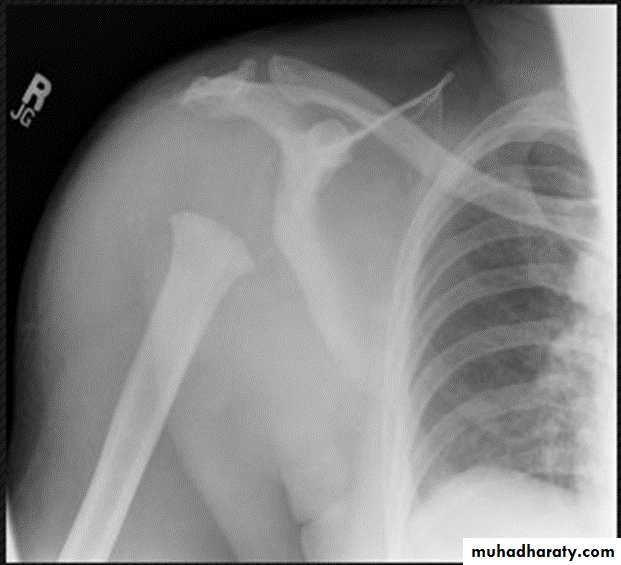

ANKYLOSING SPONDYLITIS (AS)

Seronegative spondyloarthropathy of the axial skeleton and proximal large joints.

Clinical: males >> females. HLA-B27 in 95%. Insiduous onset of back pain and stiffness. Onset: 20 years.Radiographic features:

* SI joint is the initial site of involvement:

bilateral, symmetrical

Erosions: early ,Sclerosis: intermediate , ankylosis: late

* Contiguous thoracolumbar involvement

Vertebral body "squaring": early osteitis

* Syndesmophytes

* Bamboo spine: late fusion and Bamboo spine

ligamentous ossification

*ankylosed spine (fracture)

* Enthesopathy is common(("whiskering of tuberosities )

* Arthritis of proximal joints (hip > shoulder) in 50% ,erosions and osteophytes